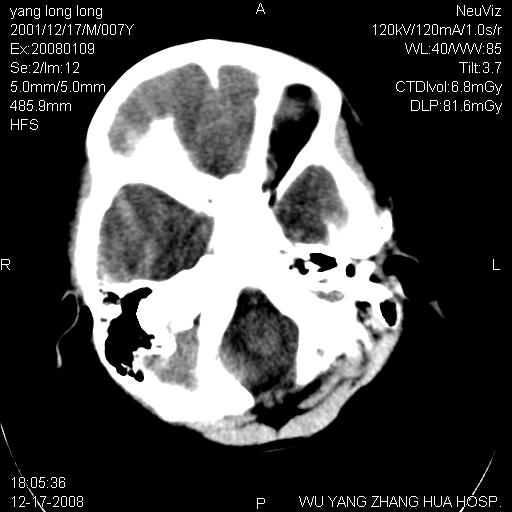

标题: PED1686:M7Y,头外伤,家人及自诉平时无任何不适。 [打印本页]

标题: PED1686:M7Y,头外伤,家人及自诉平时无任何不适。

考虑蛛网膜囊肿,请老师们看看多指导指导。

多考虑大枕大池。本例颅骨歪歪的,灶后枕骨似有膨胀征像(为蛛网膜囊肿征像),但整个左侧枕叶后方枕骨均有向后膨隆,所以暂不考虑蛛网膜囊肿。必要时随访

鉴别巨大枕大池与蛛网膜囊肿之间,倾向前者。

病变向两侧延伸,颅骨内板受压侵蚀,似有张力!!还是考虑蛛网膜囊肿!!